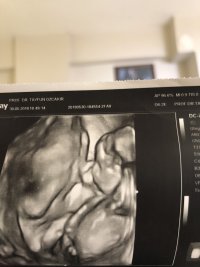

Burda 12 haftalık buna göre tahmin yaparmisiniz

Tekrar merhaba maalesef bunda da nub çıkıntısı görünmüyor. Zaten bu haftalarda bebeğin cinsiyetinde yanılma payı çok yüksek 17-18 -20 . haftalarda net olarak bebeğinizin cinsiyetini öğrenebilirsiniz. Sağlıklı gebelik süreci diliyorum.